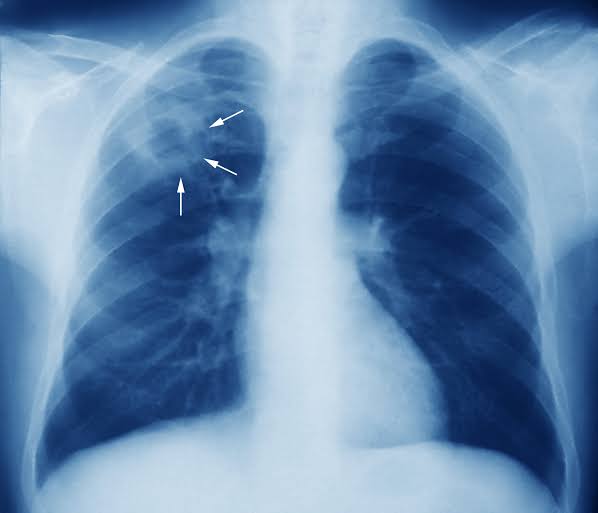

Tuberculosis (TB) is caused by bacteria (Mycobacterium tuberculosis) that most often affect the lungs. Tuberculosis is curable and preventable.